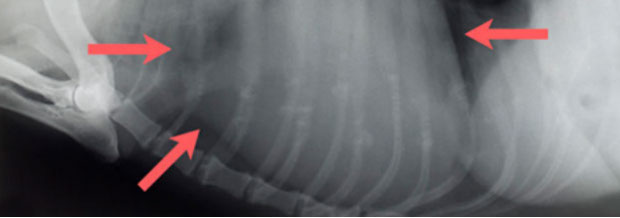

Neubildungen am Knochen, Hund